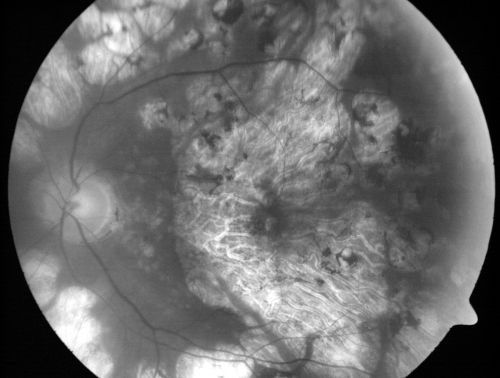

Macular and Peripheral Retinal Scarring from Diabetic Laser Done 25 years previously

72-year-old man had macular and peripheral laser done in the past(1980's)(25 years ago).  His vision, although limited, seems about stable to him.  He is diabetic for 30 years. OD is 20/160, OS  is 20/160.